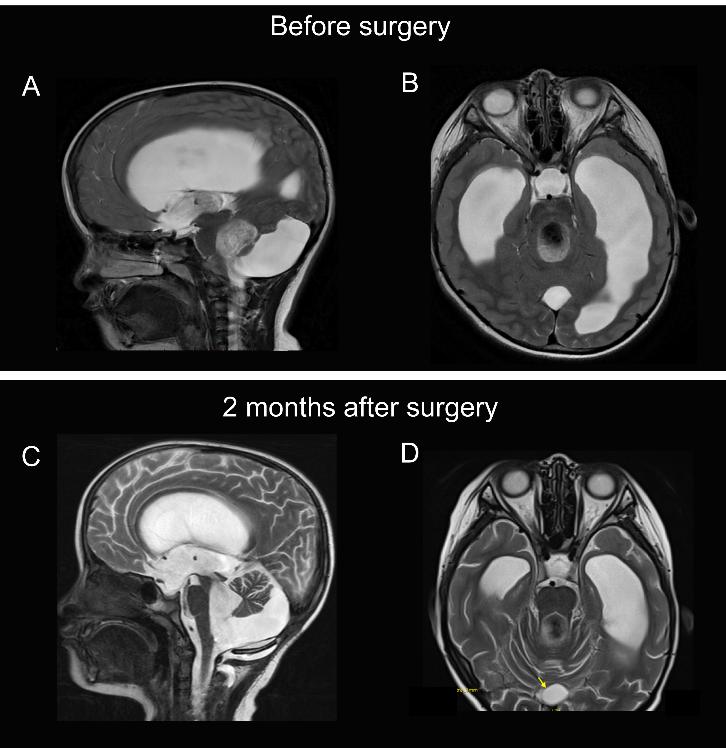

眼科检查:最佳矫正视力(Best Corrected Visual Acuity,BCVA)右眼:0.4,左眼:0.9,右眼屈光度为+1.75 DS/-1.75 DC×175°,左眼屈光度为+1.00 DS/-0.75DC×170°,双眼眼前段未见明显异常,双眼视盘高度水肿。头颅磁共振成像(magnetic resonance imaging,MRI):后颅窝、第四脑室扩大,幕上脑室明显扩张积水并轻度间质性脑水肿,小脑蚓部缺如、胼胝体及双侧小脑半球发育不良(图1A、B)。脑功能成像-脑脊液成像:中脑导水管脑脊液流速增高。诊断Dandy-Walker综合征,继发脑积水,脑水肿,右眼弱视。

术后2个月MRI(图1C, D):1)Dandy-Walker综合征治疗后复查,目前交通性脑积水,请结合临床;2)双侧桥小脑脚区、第四脑室异常信号灶,考虑少量积血可能性大,建议随访;3)后颅窝囊肿开窗术后,脑积水并轻度间质性脑水肿(较前稍好转),术区局部软组织稍肿胀(较前好转)。后患儿至神经外科再次行腰椎穿刺测颅内压150 mmH2O,结合患者的检查结果神经外科认为双眼视力下降并不考虑与颅内压升高相关。

图1 Dandy-Walker综合征患儿术前及第一次术后MRI影像

Figure 1 Preoperative and postoperative MRI images of the patient with Dandy-Walker syndrome

术前MRI,(A) T2序列矢状位:后颅窝、第四脑室扩大,幕上脑室明显扩张积水并轻度间质性脑水肿,小脑蚓部缺如;(B) T2序列水平位:胼胝体及双侧小脑半球发育不良,脑室扩张明显。后颅窝蛛网膜囊肿部分切除术后2个月MRI;(C) T2序列矢状位:后颅窝囊肿开窗术后,脑积水并轻度间质性脑水肿(较前稍好转),术区局部软组织稍肿胀(较前好转);(D) T2序列水平位:可见脑室扩张(较前好转)。

Before the first surgery, (A) Sagittal T2-weighted section: enlarged posterior cranial fossa and fourth ventricle, marked dilatation of the supratentorial ventricles with hydrocephalus and mild interstitial cerebral edema, with absence of cerebellar vermis; (B) Horizontal T2-weighted section: hypoplasia of the corpus callosum and bilateral cerebellar hemispheres, with significant ventricular dilatation. Two months after the partial resection of arachnoid cyst in posterior cranial fossa, (C) Sagittal T2-weighted section: after posterior cranial fossa cystotomy, with hydrocephalus and mild interstitial cerebral edema (slightly improved than before), and slight localized soft-tissue swelling at the operative area (improved than before); (D) Horizontal T2-weighted section: cerebral ventricle dilatation (improved than before).